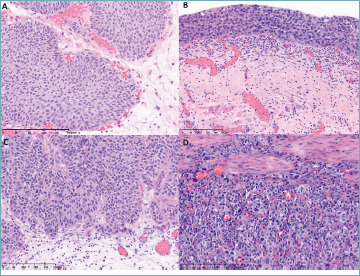

According to the current WHO classification, urothelial tumors consist of non-invasive urothelial neoplasms and invasive urothelial carcinoma which is supposed to include all tumors with invasion regardless of extent and pattern. Some pathologists are uncomfortable about such all-inclusive definition of invasive urothelial carcinoma and it is questionable whether invasiveness is a valid defining feature for primary distinction of urothelial tumors. Considering that most pathologists understand urothelial tumors based on the dual-track pathway model, we would like to raise concern that it may be necessary to rethink the validity of the current WHO classification compared to the restructuring into papillary vs non-papillary tumors. In our opinion, such restructuring would align the WHO classification with the pathogenesis model and could clarify the diagnostic terminology regarding invasiveness. The term of urothelial carcinoma in situ may also be reconsidered.

Abstract Image